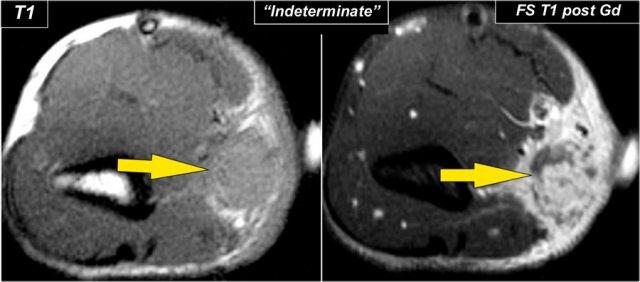

Soft Tissue Masses

Xung quanh khuỷu tay có thể xuất hiện tất cả các loại khối mô mềm, tương tự như những khối cũng được thấy ở các vị trí khác.

Nếu bạn không thể đưa ra chẩn đoán cụ thể, hãy gọi khối u là không xác định và tiến hành sinh thiết, vì trong nhiều trường hợp bạn không thể xác định được chẩn đoán.

Hình ảnh cho thấy một tổn thương hình bầu dục, trông giống như u bao thần kinh, vì nó có hình dạng thuôn dài và có vẻ như đi theo đường thần kinh, nhưng hóa ra lại là u sarcôm hoạt dịch ở một bé trai 11 tuổi.

Chỉ đưa ra chẩn đoán khi bạn chắc chắn về một chẩn đoán cụ thể như viêm túi hoạt dịch, dị dạng động tĩnh mạch, u mỡ, viêm màng hoạt dịch tế bào khổng lồ sắc tố hoặc nang hay tụ máu.